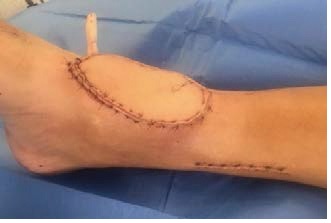

Soft tissue reconstruction, especially involving muscle, always looks bit bulky at start.

However, as the flap matures over time, its volume reduces. It usually levels with the tissue around it but can sometimes remain a bit bulky.

The colour of the flap changes over time to more or less match the skin next to it. The size and colour change is a process that takes time to settle, usually 9-12 months.

The pictures below show a timeline of a muscle flap immediately after the operation (left), after 3 months (right), and after 9 months (bottom).

Very occasionally, any bulkiness that remains can be treated, if necessary, with secondary procedures.